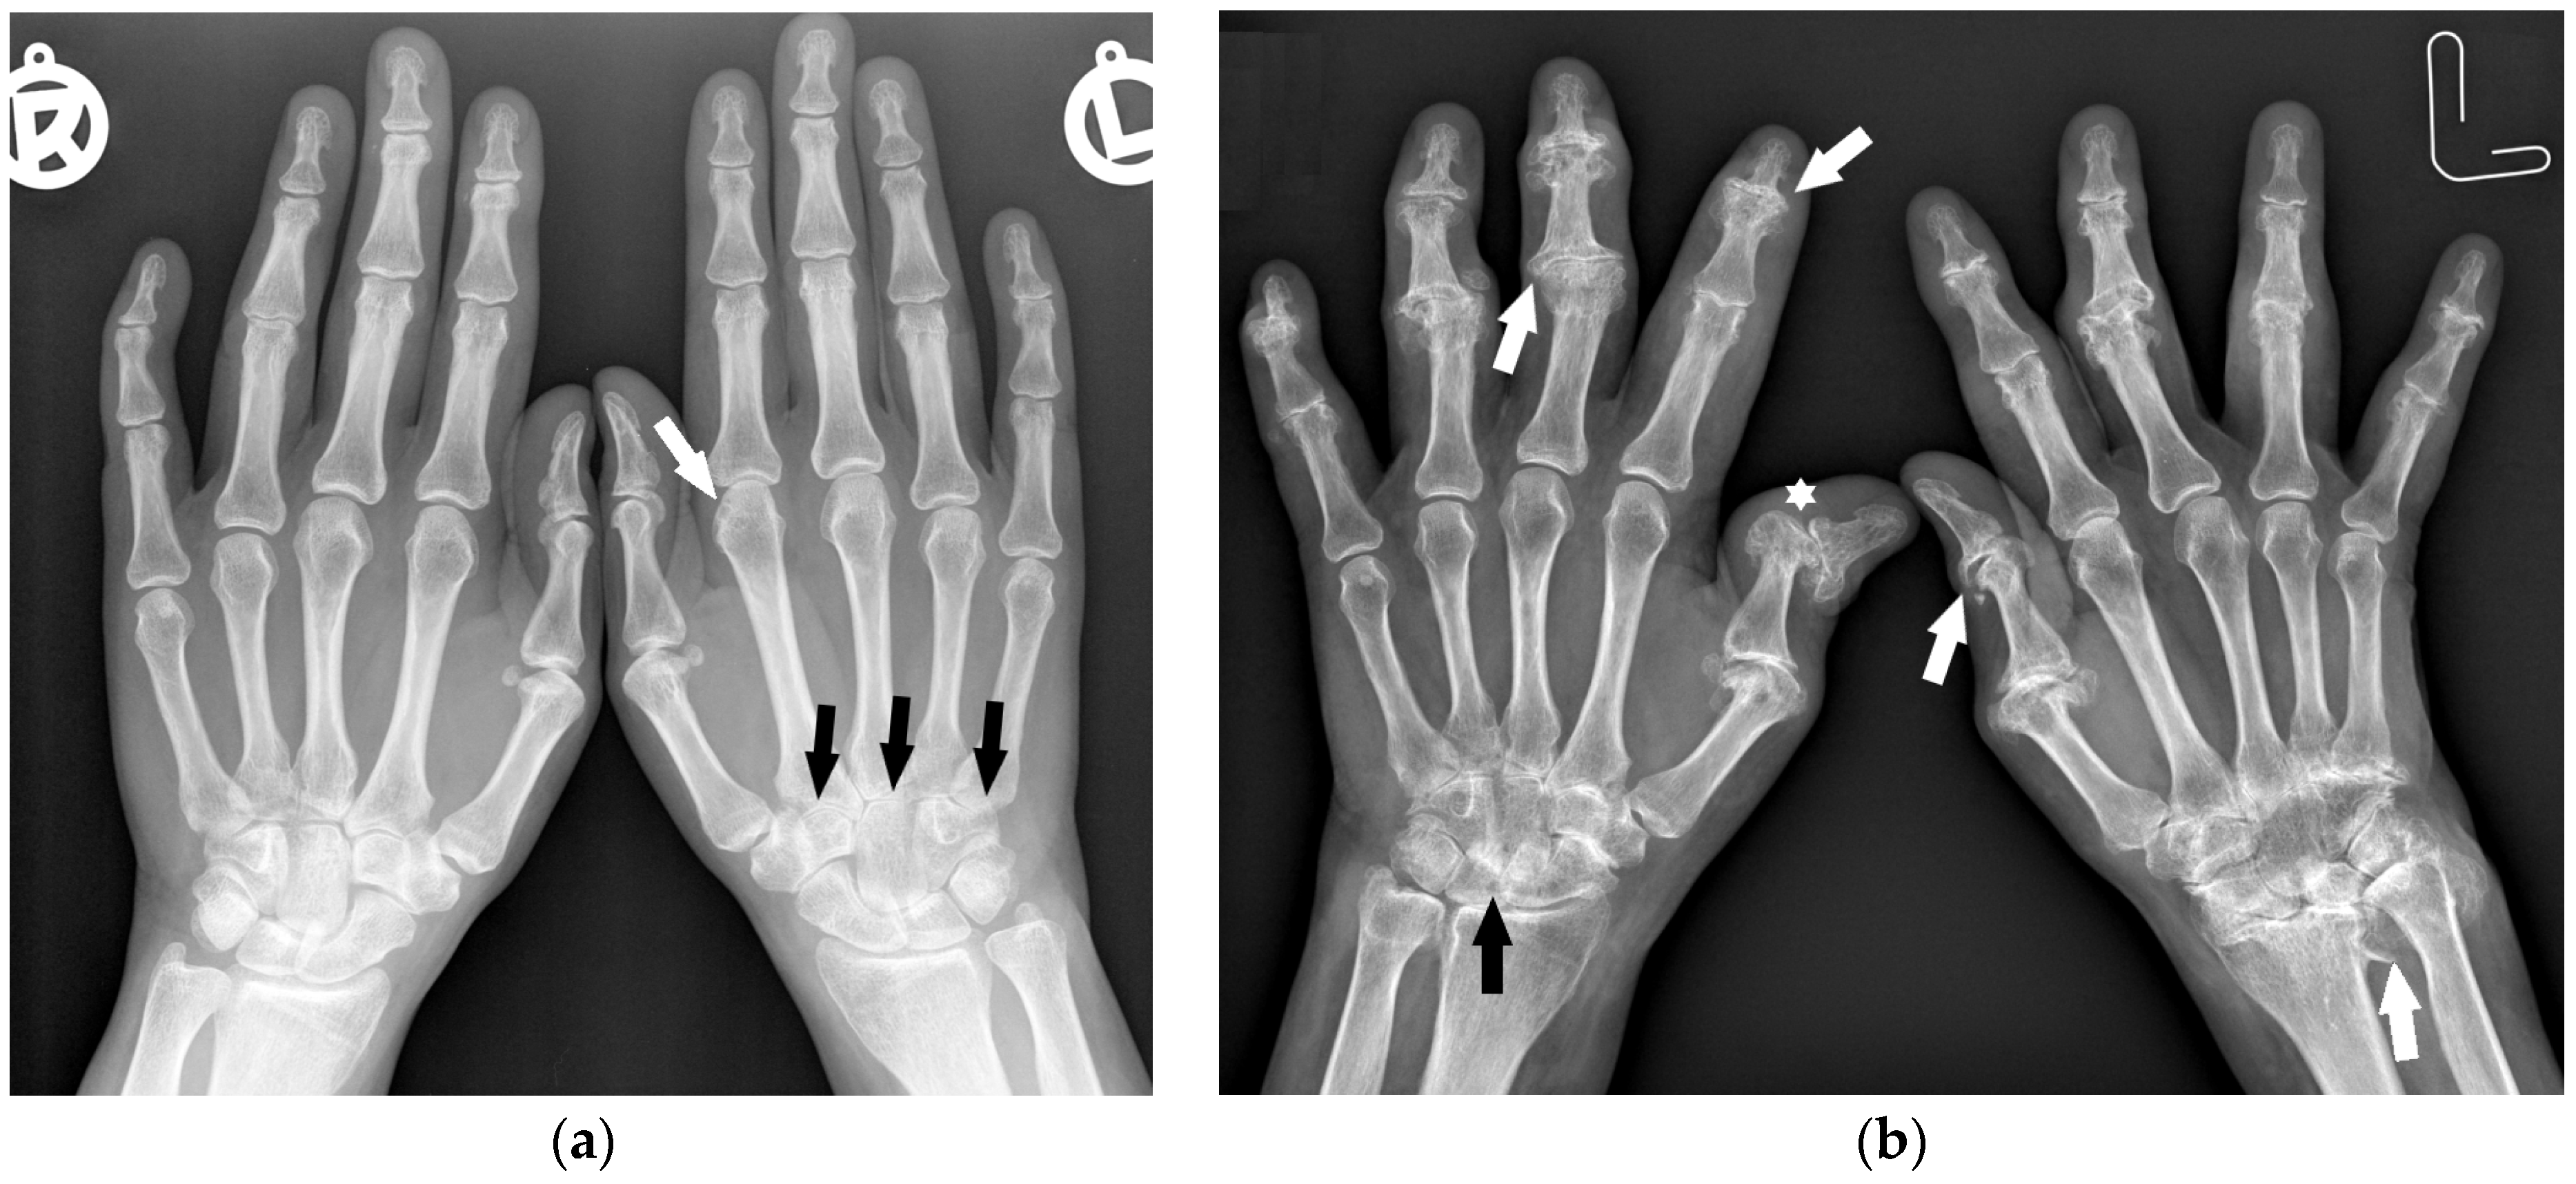

The distribution of involved joints in RA is widely described in the literature as “bilateral and symmetrical” [1,16]; however, the disease may begin as unilateral and asymmetric arthritis [15] (Figure 1).

Figure 1.

A 40-year-old female with early asymmetric seropositive rheumatoid arthritis (RA). (a) Posterior–anterior (PA) radiographs of bilateral hands show narrowing of the left radiocarpal joint (RCJ) and carpo-metatacarpal (CMC) joints (black arrows). Note the bone cyst in the left second metacarpal head and narrowing of the second metacarpophalangeal joint (MCP) (white arrow). (b) PA radiograph of the bilateral hands of the same patient, 13 years later, showed progression of the disease with increased juxta-articular osteoporosis. Note the erosive bone changes, advanced destructive changes, and joint narrowing in the RCJ and CMC joints. There are less advanced changes on the right side with joint space narrowing and bone cysts in the wrist (black arrow). Note proliferative osteoarthritic changes in left distal radioulnar joint (DRUJ) and bilateral first MCP and interphalangeal joints (white arrows). There is subluxation of the right thumb interphalangeal (IP) joint (star).